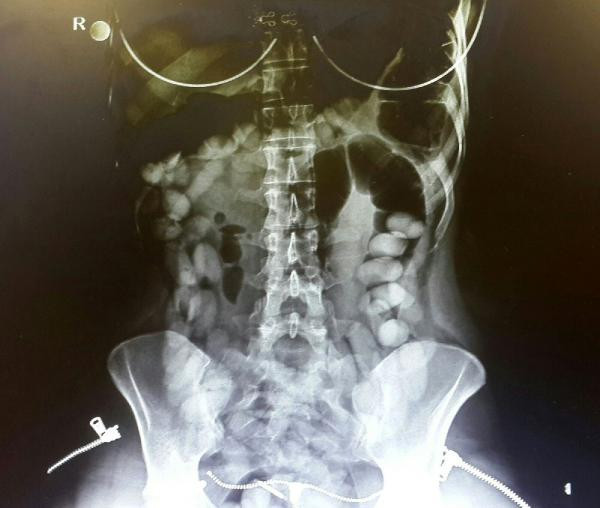

Yapılan iç muayenesinde, midesinde çok sayıda yabancı cisim olduğu görülen Maria Rodriguez, hastanede gözetim altına alındı. Kadının midesinde, her biri 10- 12 gram ağırlığında 76 kokain kapsülü tespit edildi.

Gözetim altında tutulan kadın, 4 günde 76 kapsülü doğal yollarla çıkarttı. Maria Rodriguez'in midesinden çıkan uyuşturucunun 880 gram olduğu, piyasa değerinin ise yaklaşık 350 bin TL olduğu kaydedildi.